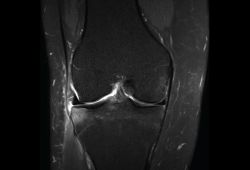

1.1. Meniscos

Figura 30. Corte de secuencia sagital T2 Fat-Sat de resonancia magnética de rodilla: menisco externo normal.

Se identifican como estructuras hipointensas en todas las secuencias, con asta anterior y posterior de morfología triangular.

Figura 31. Corte de secuencia sagital T2 Fat-Sat de resonancia magnética de rodilla: menisco interno normal.

La RM es la técnica de elección en el diagnóstico de la patología meniscal(17)(Figuras 30, 31, 32, 33, 34 y 35).